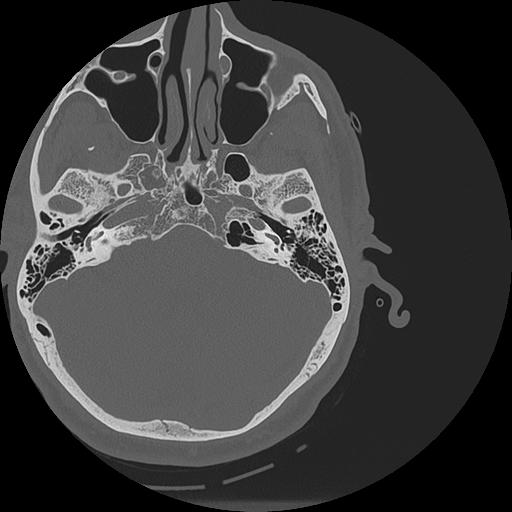

7 HUESO,,Vol,0.5,HUESO,,